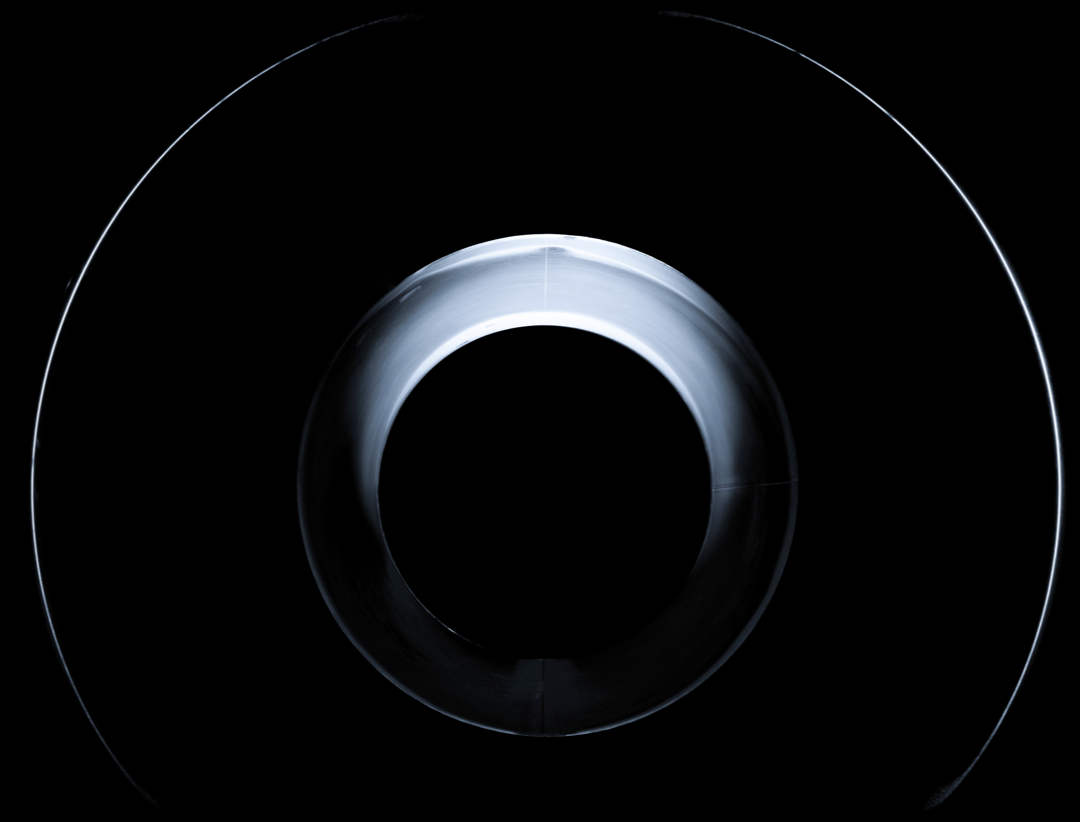

业界首创75cm超大孔径

75cm 超大孔径

较传统大孔径设备提供更多空间,提供更舒适的扫描环境。

超大孔径净磁体

全新97cm超大孔径净磁体技术,既可以实现75cm的超大孔径,也可以实现系统的高性能表现。15%的超导线绕制密度增加配合科研级匀场技术,实现比传统大孔径更优异的磁场均匀度。